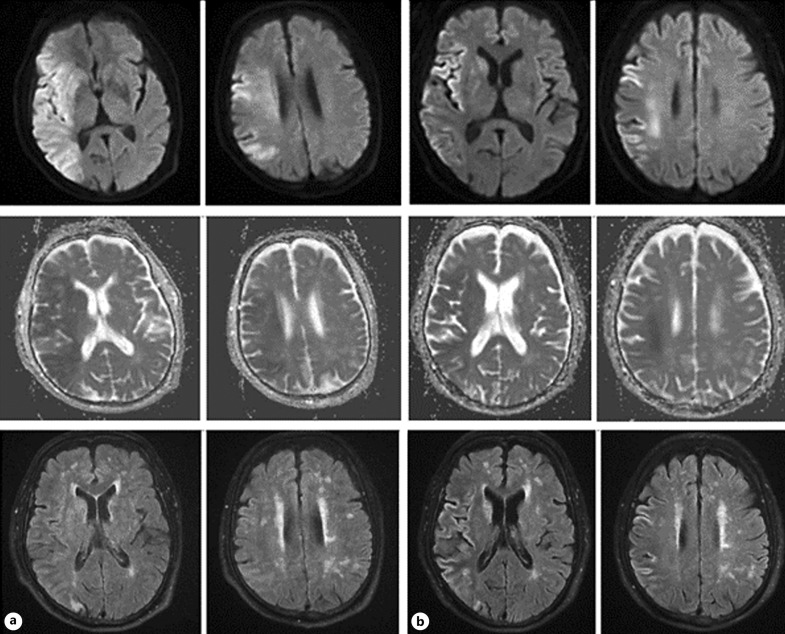

Case presentation: A 58-year-old male presented with a generalized tonic-clonic seizure. Emergent magnetic resonance imaging (MRI) revealed an extremely large infarction lesion in the right hemisphere with an Alberta Stroke Program Early Computed Tomographic Score (ASPECTS) value of 2 and occlusion of the terminal right internal carotid artery. The patient was immediately transferred to the Digital Subtraction Angiography (DSA) Unit for endovascular treatment with a stent retriever. After a rapid successful reperfusion with expanded treatment in cerebral infarction (eTICI) score of 3, the patient promptly recovered 24 h after the procedure. A brain MRI was repeated after 8 days of admission, and interestingly, the DWI lesion showed significant reversal. The modified Rankin scale (mRS) at discharge was 2 and 1 at 90-day follow-up, respectively.